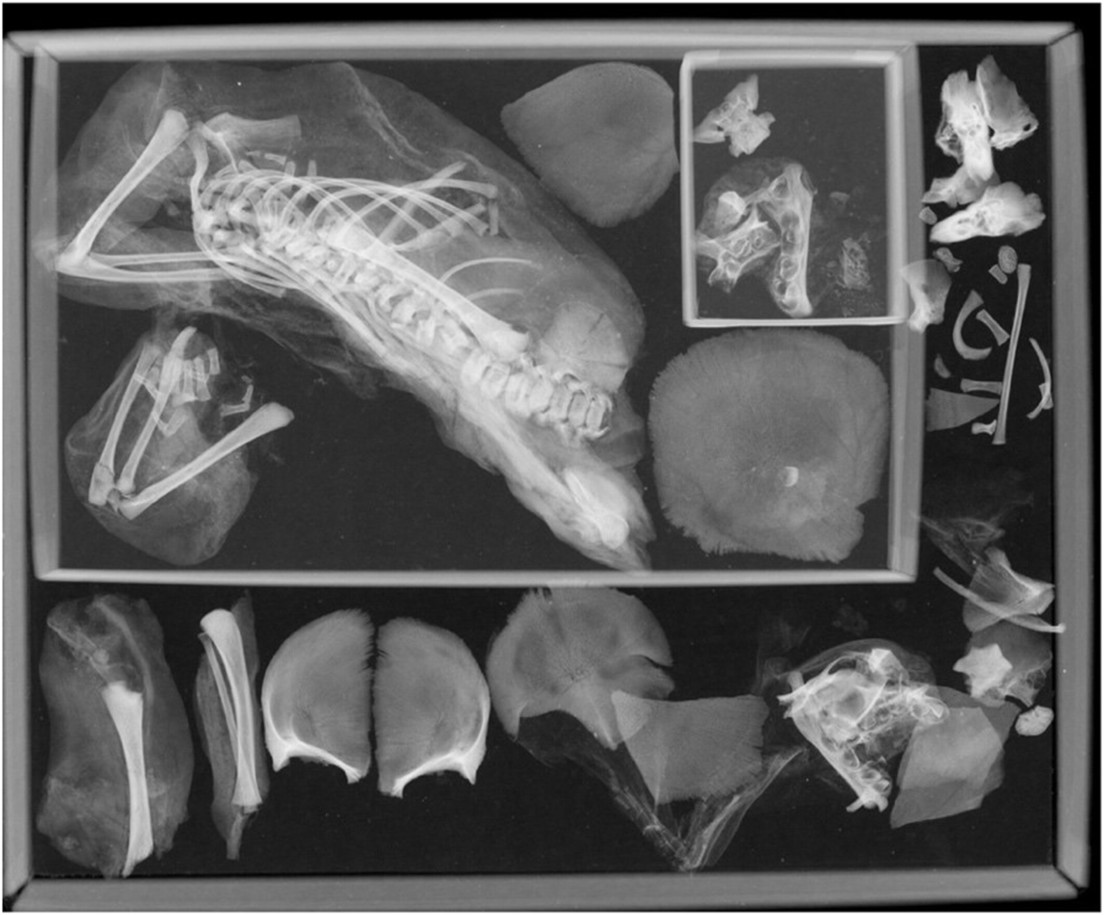

Los autores de un estudio revisaron a una momia egipcia, de una adolescente que murió durante el parto, después de más de un siglo, y le realizaron una tomografía computarizada del cuerpo, que reveló la presencia de un segundo feto en la cavidad torácica de la mujer, lo que indicaba que estaba embarazada de gemelos, según un artículo publicado en International Journal of Osteoarchaeology.

La cabeza del primer bebé quedó atrapada en el canal del parto, lo que provocó la muerte tanto de los bebés como de la madre, informó IFL Science.

El estudio descubrió que, al morir, la joven fue momificada junto con el niño, cuyos restos fueron colocados entre las piernas de la madre, a excepción de la cabeza, cuyos huesos quedaron dentro de la pelvis. Es decir, el niño fue decapitado durante el parto.

La muerte del bebé y su madre probablemente ocurrieron debido al llamado parto de nalgas, donde el bebé sale con los pies primero, lo que hace el proceso mucho más complicado y peligroso.

Los investigadores suponen que con el tiempo el cuerpo de la fallecida se descompuso y el feto se desplazó desde el útero hasta la cavidad torácica.

La joven pesaba entre 45 y 55 kilogramos. Los científicos estiman que la mujer tenía entre 34 y 40 semanas de embarazo cuando comenzó el parto.